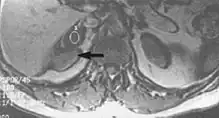

Flow

Flow can manifest as either an altered intravascular signal (flow enhancement or flow-related signal loss), or as flow-related artifacts (ghost images or spatial misregistration). Flow enhancement, also known as inflow effect, is caused by fully magnetised protons entering the imaged slice while the stationary protons have not fully regained their magnetization.[1] The fully magnetized protons yield a high signal in comparison with the rest of the surroundings. High velocity flow causes the protons entering the image to be removed from it by the time the 180-degree pulse is administered. The effect is that these protons do not contribute to the echo and are registered as a signal void or flow-related signal loss (Fig. 2).[1] Spatial misregistration manifests as displacement of an intravascular signal owing to position encoding of a voxel in the phase direction preceding frequency encoding by time TE/2.The intensity of the artifact is dependent on the signal intensity from the vessel, and is less apparent with increased TE.[1]